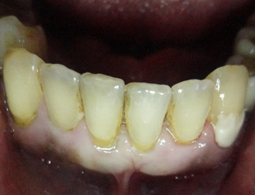

Esta paciente veio ao consultório com a indicação de uma raspagem nesta região. Pois segundo seu Dentista, sua gengiva esta inflamada. Um exame radiográfico foi realizado, mostrando uma grande perda de osso, os dentes apresentavam uma grande mobilidade, com um prognóstico muito sóbrio. O caso da paciente, foi minuciosamente discutida com a paciente, mostrado que os dentes da bateria inferior anterior estavam perdidos, não haveria meios mais, de serem recuperados. Foi um choque no início para a paciente, contudo após um exame geral em sua boca, mostrando as profundas bolsas intraósseas, com inflamações generalizadas, e o risco que ela corria, não somente pela perda dos dentes, mas comprometimentos gerais incluindo problemas sérios cardíacos, ela se conscientizou da necessidade urgente de tratamento.

No início da profilaxia pré-cirúrgica, com as pontas de ultrassom, podemos demonstrar a paciente a necessidade do procedimento indicado. Os dentes praticamente seriam removidos apenas com uma profilaxia rigorosa. Em certos casos, e dependendo dos pacientes, é importante mostrar as alterações patológicas, assim como documentar os procedimentos, que forem realizados. Os dentes foram extraídos, pois, estavam condenados. Apaciente não usava, pois estavam moles e doíam.